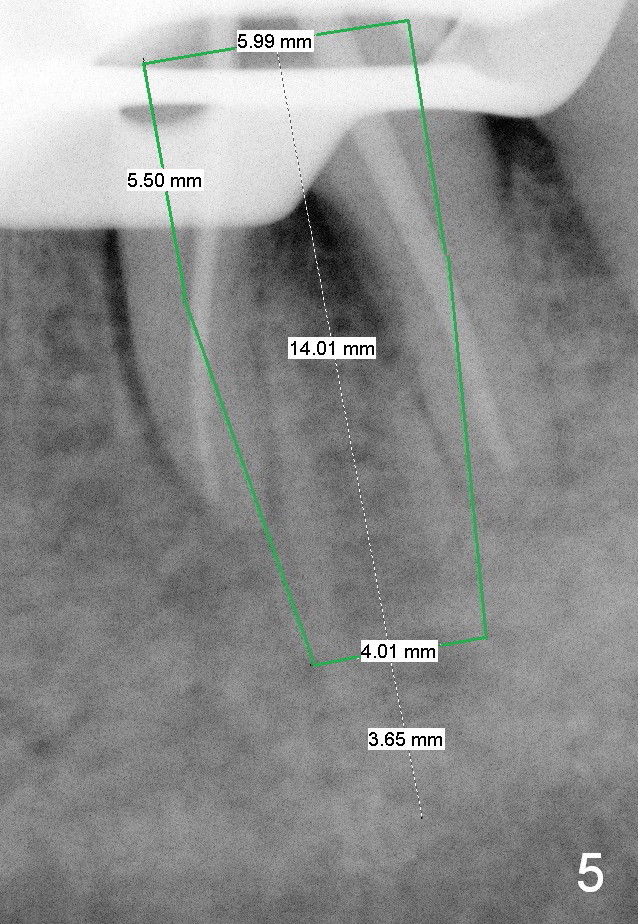

A 59-year-old lady has history of periodontal disease and bruxism.  The tooth #19 has pulpitis after unsuccessful DO composite (Fig.1 *) and requires root canal therapy (Fig.2).  Six months later, a fistula is found to communicate with the furca (Fig.3 *: gutta percha).  Less than 3 years, the furca enlarges with symptoms of infection (Fig.4 *).  She works out of state. The Principle of No Implant, No Extraction is adhered.  Since she is of short statue, the bone height is relatively limited.  A 6x14 mm tissue-level implant is appropriate (Fig.5, one piece).  Sensor 1 may be proper for her small mouth.  When the bottom of the socket is large and close to the Inferior Alveolar Nerve, can an immediate implant be placed?